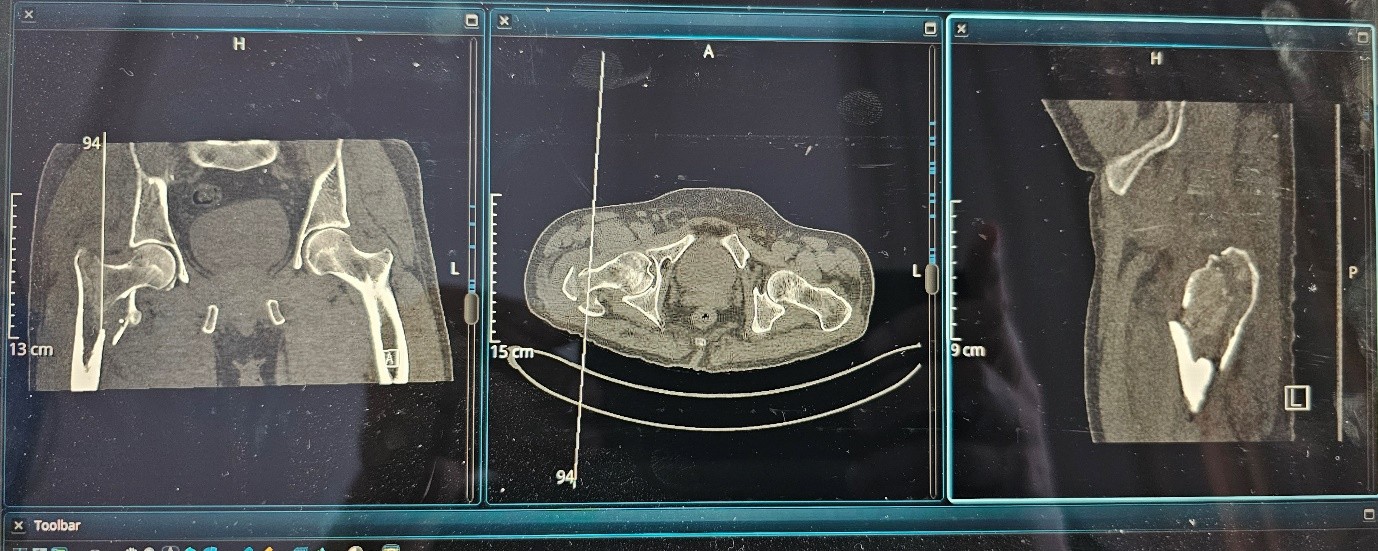

Postoperative Imaging and Diagnosis:

Postoperative X-rays were inconclusive due to suboptimal views. To evaluate screw position and fracture alignment more accurately, a CT scan was performed. The CT revealed that the cephalic screw had cut through the femoral neck, protruding medially outside the cortex, and continued into the femoral head—confirming a case of cut-through.

Post first surgery :

Fig 3

Fig 4

Fig 5

Figure 3

Figure 4

Figure 5